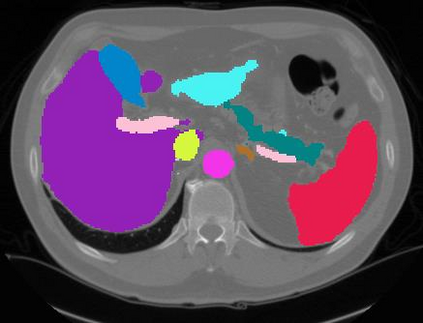

Vision transformers, with their ability to more efficiently model long-range context, have demonstrated impressive accuracy gains in several computer vision and medical image analysis tasks including segmentation. However, such methods need large labeled datasets for training, which is hard to obtain for medical image analysis. Self-supervised learning (SSL) has demonstrated success in medical image segmentation using convolutional networks. In this work, we developed a \underline{s}elf-distillation learning with \underline{m}asked \underline{i}mage modeling method to perform SSL for vision \underline{t}ransformers (SMIT) applied to 3D multi-organ segmentation from CT and MRI. Our contribution is a dense pixel-wise regression within masked patches called masked image prediction, which we combined with masked patch token distillation as pretext task to pre-train vision transformers. We show our approach is more accurate and requires fewer fine tuning datasets than other pretext tasks. Unlike prior medical image methods, which typically used image sets arising from disease sites and imaging modalities corresponding to the target tasks, we used 3,643 CT scans (602,708 images) arising from head and neck, lung, and kidney cancers as well as COVID-19 for pre-training and applied it to abdominal organs segmentation from MRI pancreatic cancer patients as well as publicly available 13 different abdominal organs segmentation from CT. Our method showed clear accuracy improvement (average DSC of 0.875 from MRI and 0.878 from CT) with reduced requirement for fine-tuning datasets over commonly used pretext tasks. Extensive comparisons against multiple current SSL methods were done. Code will be made available upon acceptance for publication.